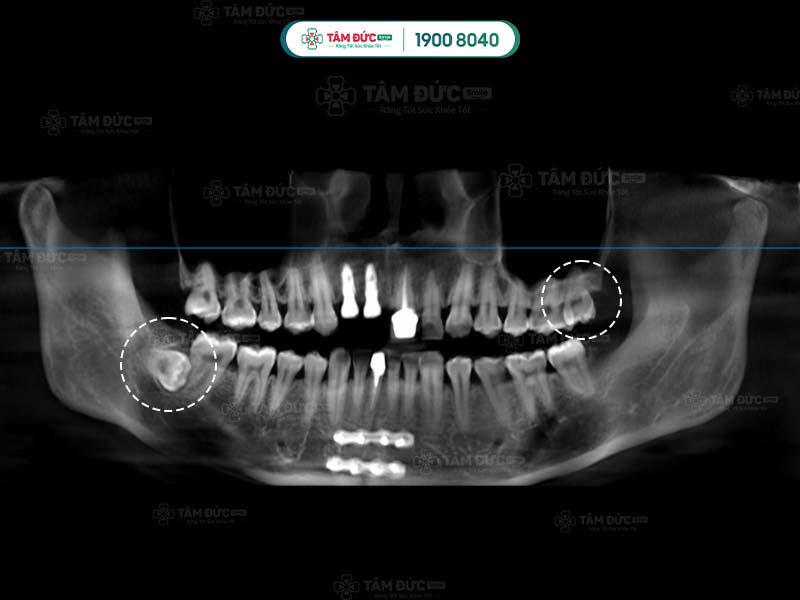

Răng khôn thường mọc ở phía sâu trong khoang miệng, sau răng hàm thứ 2. Răng khôn thường mọc ở 4 vị trí góc miệng: hàm trên trái, hàm trên phải, hàm dưới trái và hàm dưới phải.

Một số ít trường hợp, răng khôn không mọc ở cả 4 vị trí. Có người chỉ mọc 2 chiếc, có người chỉ mọc 1 chiếc. Quý khách không thể tự đếm hay nhìn thấy răng khôn mọc ngầm bằng mắt thường, mà cần phải thông qua chụp phim X-Quang.

Đầu tiên là bước thăm khám lâm sàng để thu thập những chỉ số cần thiết như: chỉ số đông máu, số lượng tiểu cầu… Tiếp đến, Quý khách sẽ được chụp X-quang nhằm xác định răng khôn có mấy chân và hình dáng của chân răng khôn.

Sau khi nhận kết quả chụp phim, bác sĩ tiến hành đánh giá tình trạng và độ khó của phẫu thuật. Tiếp đến, Quý khách sẽ được tiêm thuốc gây tê tại chỗ. Với trường hợp răng khôn dễ nhổ: bác sĩ tiến hành rạch trên nướu, làm sạch vùng phẫu thuật để tiếp cận và nhổ bỏ răng khôn. Trường hợp khó hơn: răng khôn có nhiều chân thì cuộc phẫu thuật có thể kéo dài. Lúc này bác sĩ sẽ rạch và cắt từng chân của răng khôn để đảm bảo an toàn.